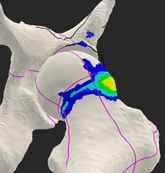

MRI scan Showing Labrum Tear

FAI is diagnosed by a careful physical examination by your surgeon in conjunction with diagnostic studies such as x-rays, MRI scans, and CT scans. Some patients may be advised to undergo a diagnostic and possible therapeutic injection of the hip joint. This can be performed using fluoroscopy (x-ray) or ultrasound to guide the injection into the joint space. This is often best performed by your treating surgeon and can be performed in the office with minimal discomfort.